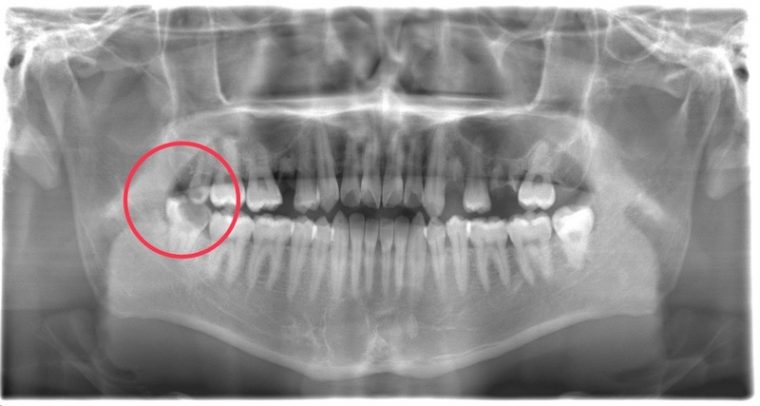

CASE 13

| 年齢・性別 | 32歳・男性 |

| 主訴 | 左上下の奥歯が痛い |

| 抜歯期間 | 60分 |

| 抜歯費用 | 約6,000円 別途CT撮影で3,000円 (2022年8月現在) |

| 抜歯内容 | 左上下の親知らず、左下7抜歯 |

| 治療方針 |

初診時は左上下の痛みでご来院されました。全体的に歯石を除去した後、主訴の解決のために虫歯が進行している左上下の親知らずと左下7の抜歯を行いました。 歯石除去と抜歯を行った後は、痛みが引いてきて口腔内の環境が変わったことに喜んでくれました。 今後は歯ぐきの状態を良くしながら、虫歯や欠損部の治療を行っていきます。 |